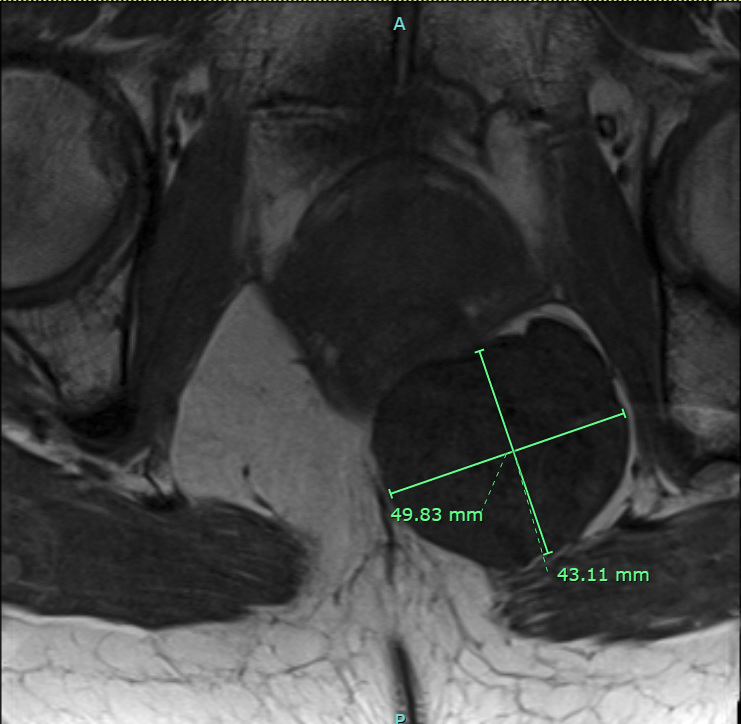

T1 weighted MRI, transverse image of well-circumscribed, low signal tumor along the undersurface of the posterior levator ani muscle.